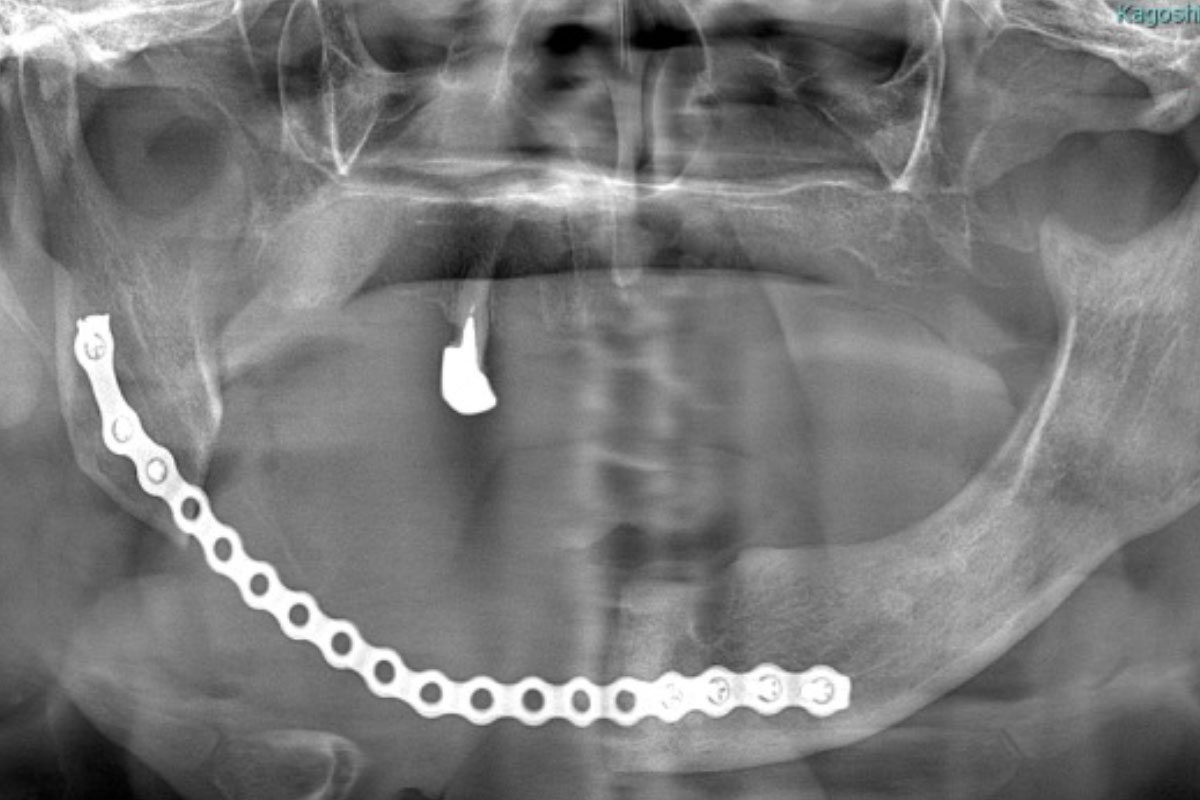

画像検査(パノラマX線、CT、MRI、骨シンチグラフィーなどの核医学検査)、血液検査、病理組織検査などを行います。

主に保存的な治療(洗浄、抗菌薬の投与)、外科的な治療(壊死している骨を除去する手術、顎の骨を切りとる手術、など)に分けられます。補助的な治療(高気圧酸素療法)を追加する事もあります。顎の骨を切る手術を行う場合は、金属のプレートや皮弁(自分の脚の骨など)による再建を行い、口を開ける、義歯を入れてご飯を食べる、などの口腔の機能を維持するようにしています。